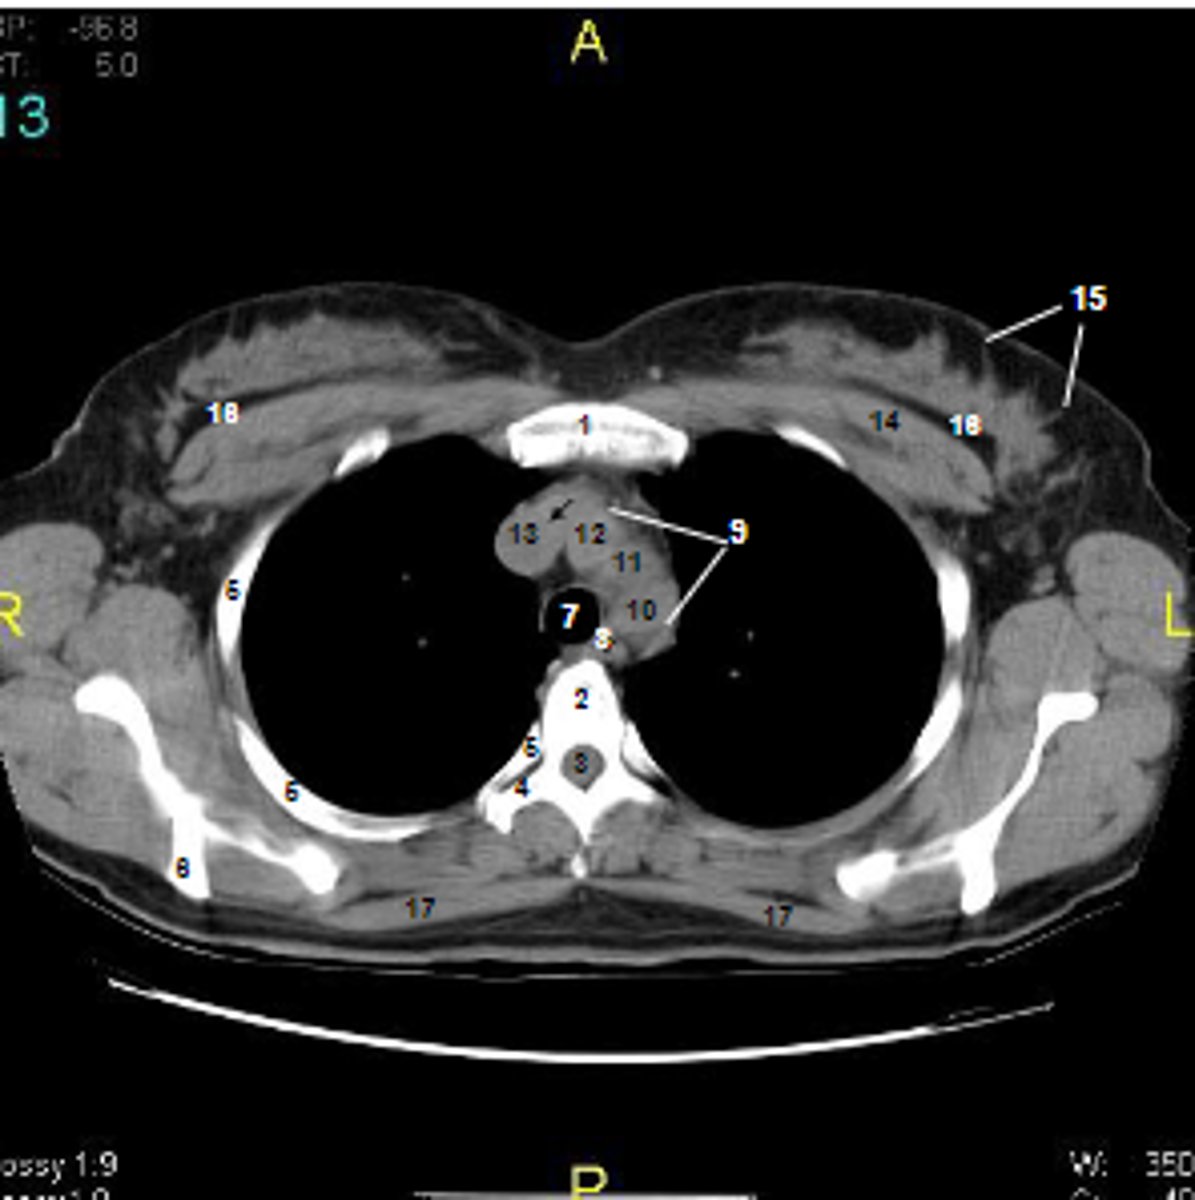

1

at what number is the sternum

2

at what number is the vertebral body

3

at what number is the vertebral canal/ spinal cord

4

at what number is the transverse process of vertebra

5

at what number is the rib

6

at what number is the spine of scapula

7

at what number is the trachea

8

at what number is the esophagus

9

at what number is the arch of aorta

10

at what number is the left subclavian artery

11

at what number is the common carotid artery

12

at what number is the brachiocephalic trunk

13

at what number is the superior vena cava

14

at what number is pectoralis major

15

at what number are Cooper's ligaments

16

at what number is the retromammary space

17

at what number is trapezius